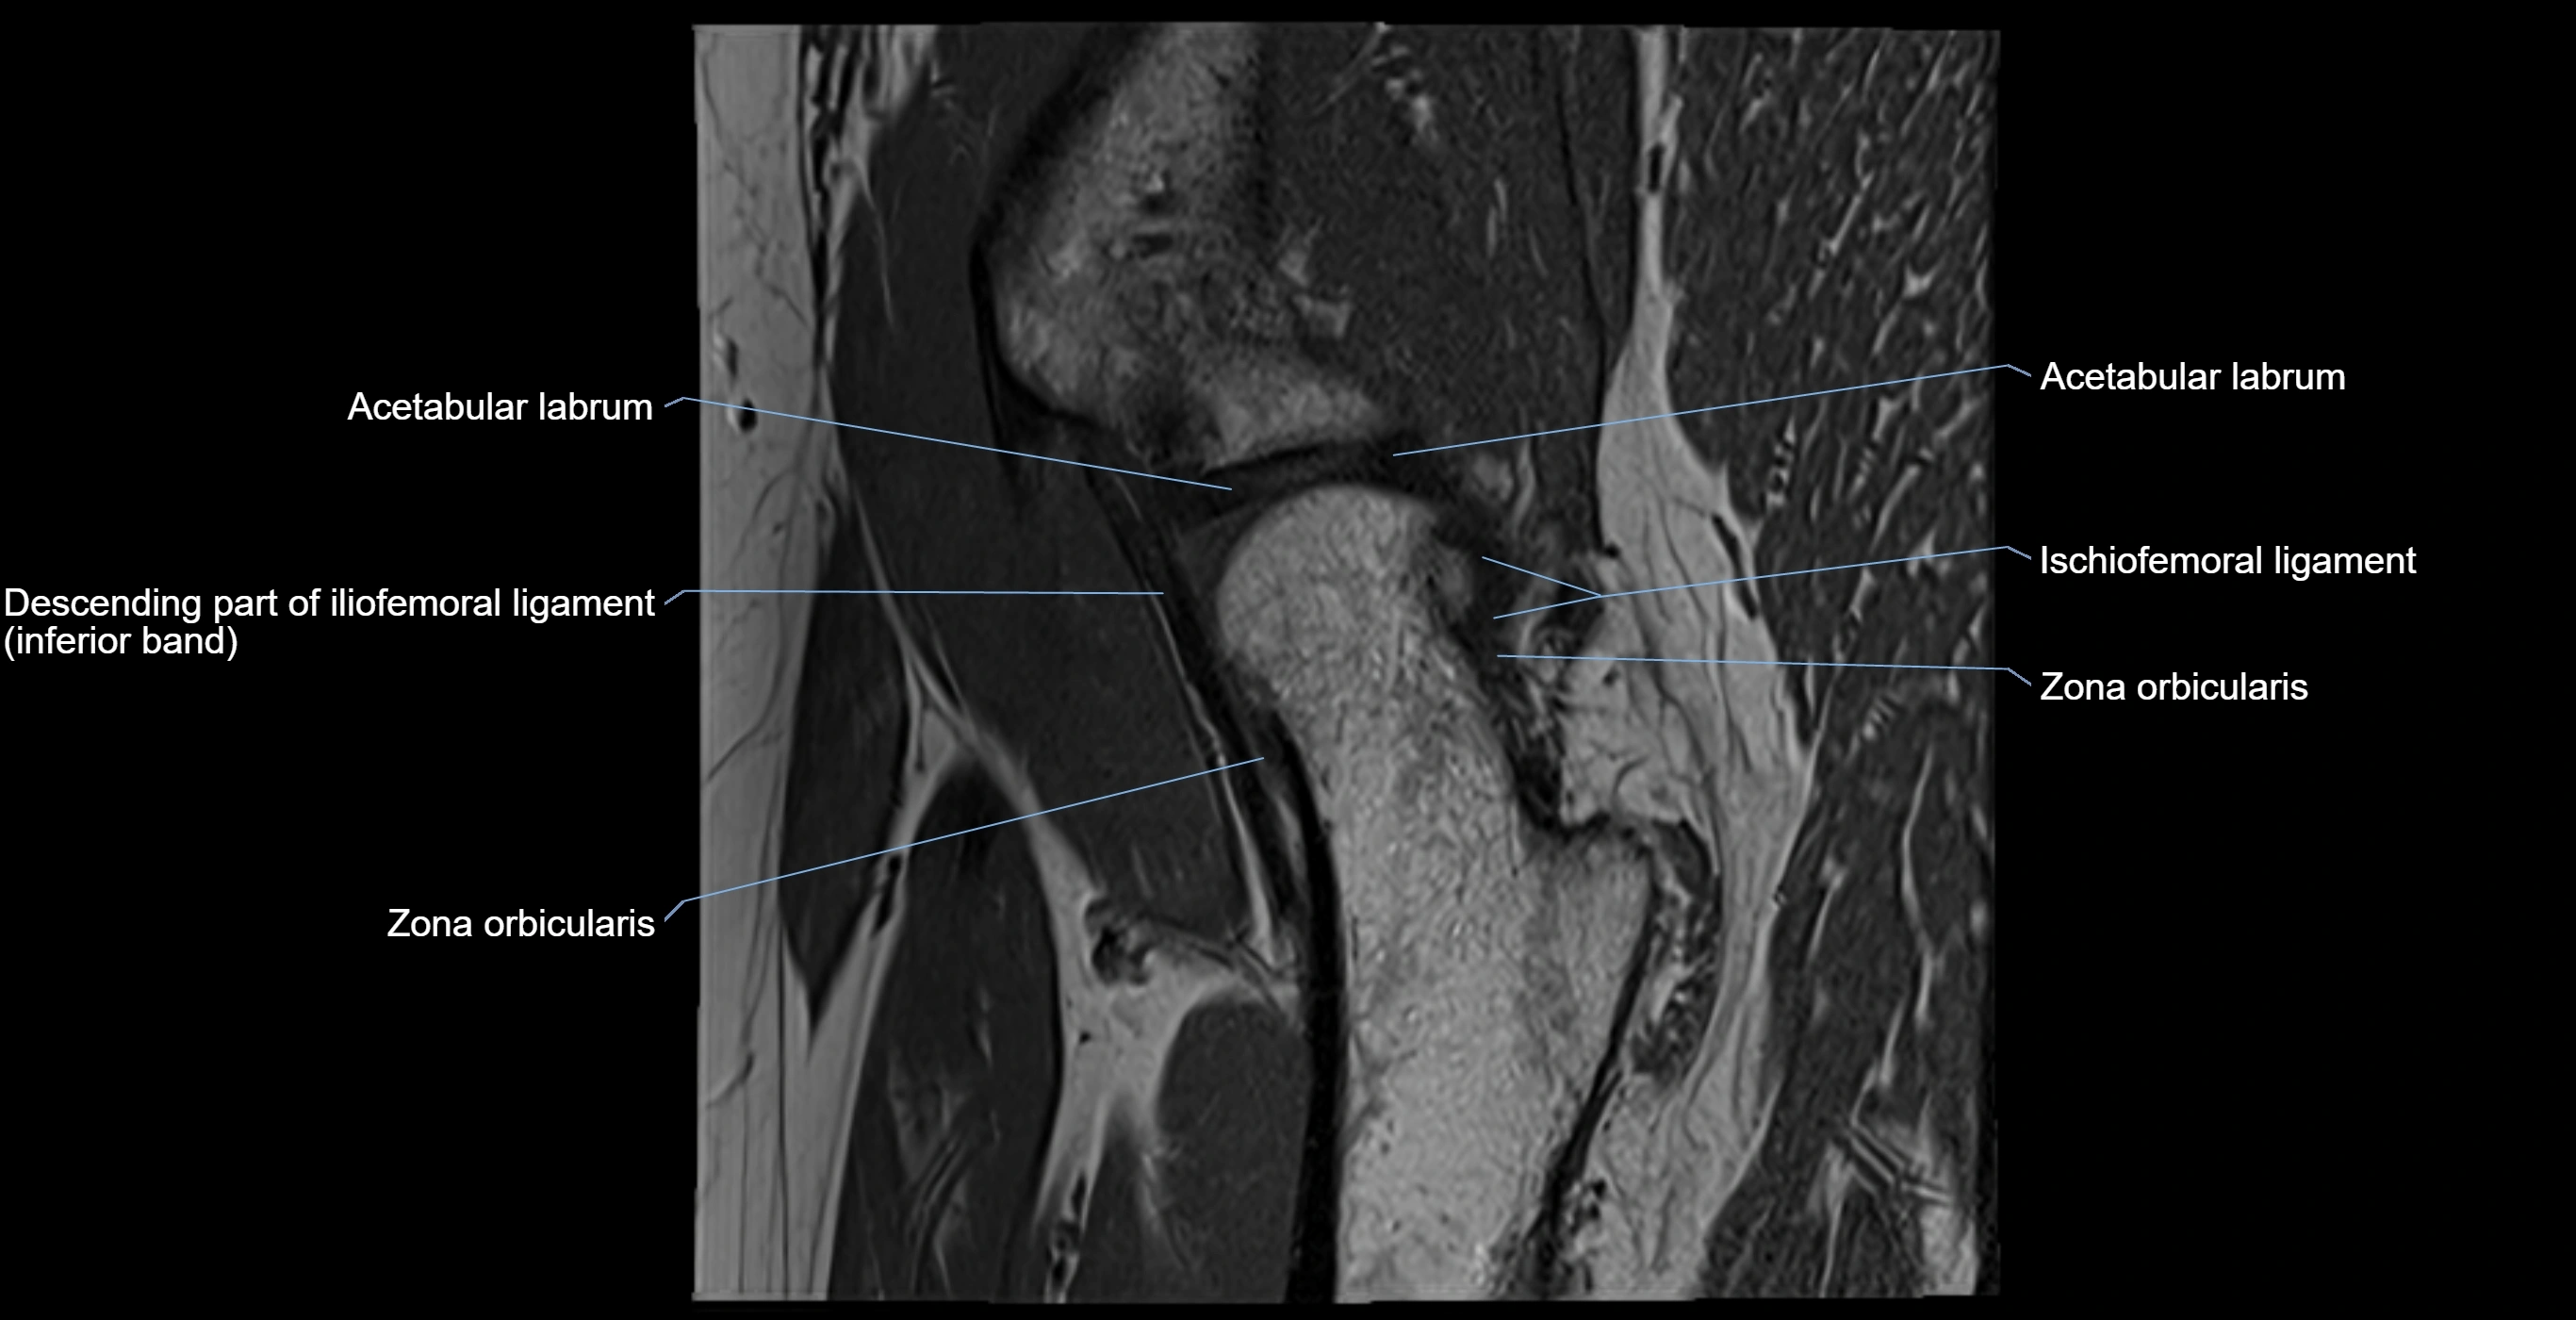

MRI image

image